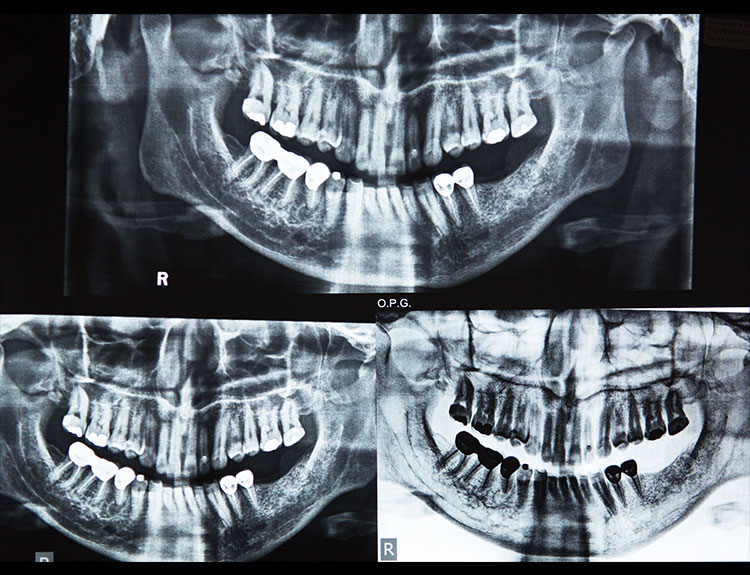

Missing teeth can affect not just your smile, but also your confidence, chewing ability, and overall oral health. At Dental Que, we offer advanced Dental Implants in Punjabi Bagh, West Delhi, designed to restore the look, feel, and function of natural teeth with long-lasting results.

Dental implants are artificial tooth roots made of medical-grade titanium that are surgically placed into the jawbone. Once the implant integrates with the bone, a crown is fixed on top, giving you a strong, natural-looking replacement tooth.

When compared to bridges or dentures, dental implants offer unmatched comfort and longevity.